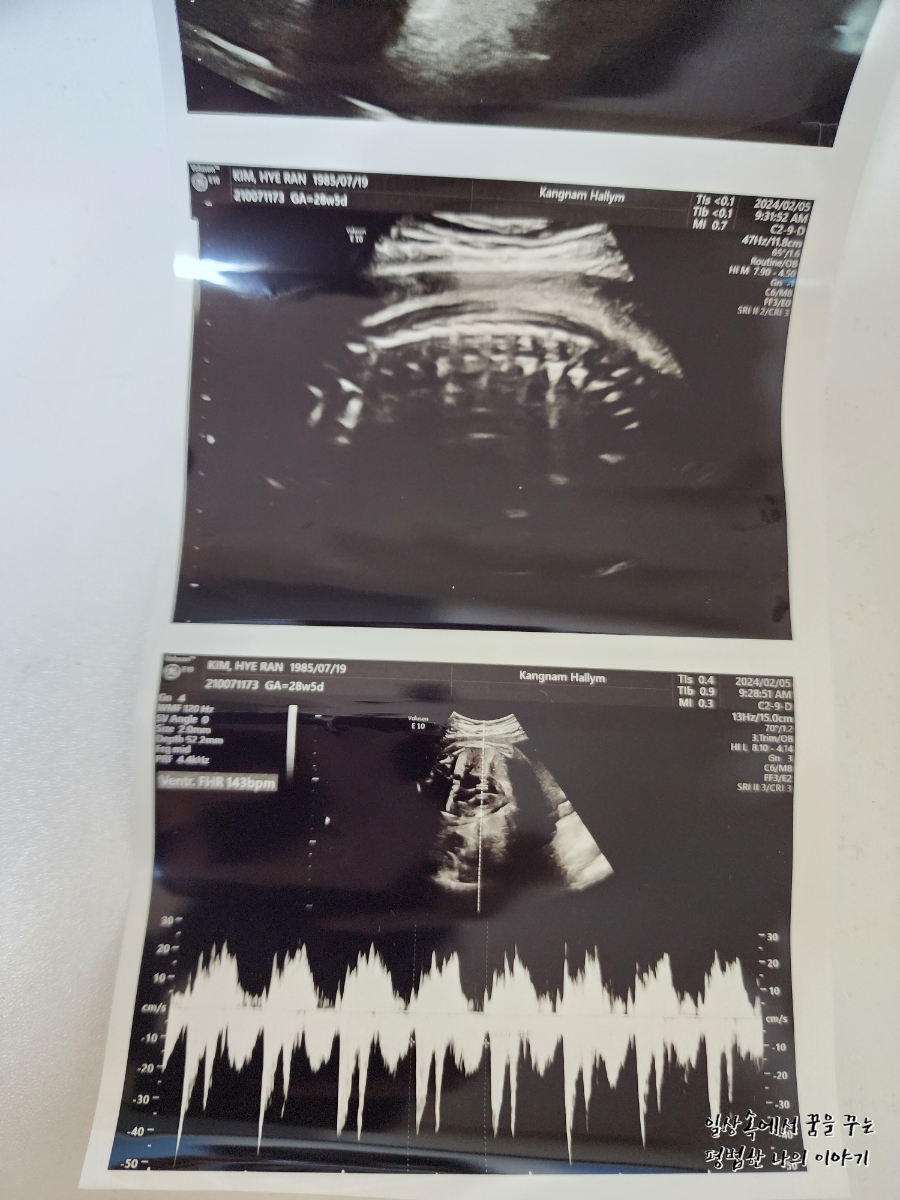

2024년 2월 5일(월요일)

BPD(Biparietal Diameter, 위에서 볼 때 태아 머리 단면의 가장 긴 길이): 7.22cm

HC(Head Circumference, 태아 머리둘레): 26.4cm

AC(Abdominal Circumference, 배 둘레): 27.27cm

EDD(Expected Date of Delivery, 출산 예정일): 2024년 4월 24일

FL(Femur Length, 허벅지뼈 길이): 5.47cm

GA(Gestational Age, 임신 주차): 28주 차 5일

EFW(Estimated Fatal Weight, 태아 예상 체중)=EBW(Estimated Body Weight): 1571g

FHR(Fetal Heart Rate, 심장박동 수): 143bpm

CL(Cervical Length, 자궁경부 길이): 정상

AF(Amniotic Fluid, 양수): 정상

이번에 오랜만에 보는 초음파라 얼굴이라도 볼 수 있으려나 내심 기대하고 갔는데 얼굴을 아래쪽으로 향한 채로 뒤돌아 있어서 얼굴 보기가 쉽지 않았다. 그나마 막판에 두 손으로 얼굴을 살짝 가린 채 하품하고 있는 모습을 보여줬다. 남편 말로는 첫째보다 볼살이 더 많은 것 같다며 왠지 첫째보다 더 클 것 같다고... 무럭무럭 잘 자라줘서 고마워.